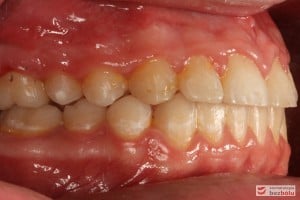

Rodzice zgłosili się z pacjentem celem rutynowej kontroli ortodontycznej. Wykonano OPG i po analizie modeli diagnostycznych stwierdzono brak miejsca dla wyrzynania dolnej prawej piątki stałej oraz zwężenie szczęki wraz z rotacją górnych zębów szóstych. W łuku górnym w pierwszym etapie leczenia zastosowano Rotator, celem odrotowania 6-tek stałych oraz ekspansji łuku w wymiarze poprzecznym. Następnie zamontowano aparat stały metalowy do uszeregowania zębów w łuku. W łuku dolnym miejsce odtwarzano stosując aparat stały i odpowiednią mechanikę leczenia. Leczenie aktywne trwało 3,5 roku, po czym zastosowano terapię retencyjną (retainer stały w żuchwie oraz Płytkę Hawley’a w szczęce).